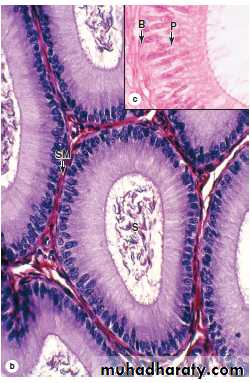

(b) The columnar epithelium of the epididymal duct is surrounded by a thin circular layer of smooth muscle (SM) cells and its lumen contains sperm (S). The smooth muscle becomes thicker and a longitudinal layer develops in the body and tail of the epididymis. X400. H&E.

(c) The inset photo shows the epithelium with tall principal cells (P) with stereocilia and fewer small basal stem cells (B).

Intraepithelial lymphocytes are also commonly seen in the epididymal duct. X500. H&E.